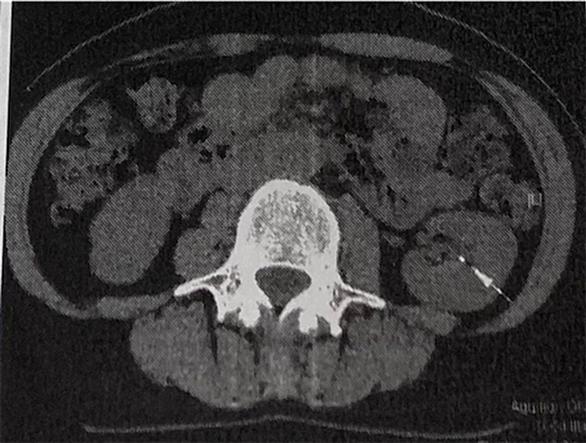

生まれて初めて病院に入院しました。入院の日は我が庭の主役はハナカイドウでした。桜の散る中を病院まで歩いていきました。 入院の目的は腎臓結石の除去手術です。すごく痛いので有名な発作は幸いにもまだ起きていませんでした。手術は内視鏡手術で尿道から内視鏡を腎臓まで差し込みレーザー光線で結石を破壊して取り出すというコワイ話を聞かされました。 まず手術前日に入院。ゆっくり寝られると思っていたら、その期待は無理でした。病院は想像していたよりずっとやかましいところです。機械音、足音、同じ病室の患者のイビキ。特に相部屋の老人が肺炎で夜中に凄まじい咳をし痰を吐きます。結局「もう死んだ方がマシ」とうめきながらICU…